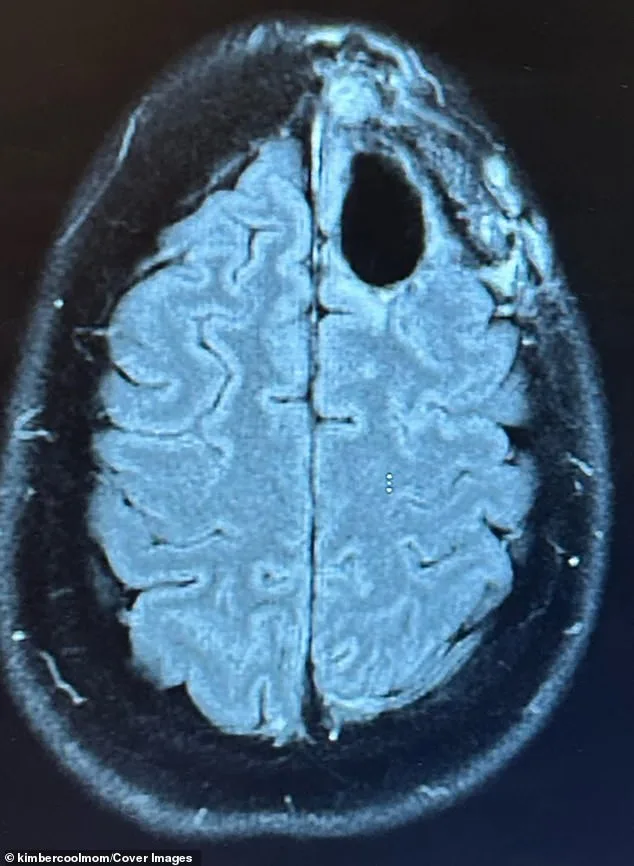

Pelling's journey began with sudden night terrors, crushing fatigue, and persistent brain fog. When her family doctor suspected seizures, she was rushed to the hospital for an MRI, which revealed a lime-sized tumor in her frontal lobe. A biopsy confirmed the worst: a grade-four astrocytoma, a cancer with a median survival rate of around 31 months. The prognosis was grim, but Pelling refused to accept it. 'I have babies at home. I can't leave them,' she said. 'But I felt this quiet voice telling me not to give up.'

Conventional treatment followed. Pelling endured surgery to remove the tumor, followed by five weeks of radiation and months of chemotherapy. The regimen left her bedridden, battling fatigue, hair loss, and brain fog. For a time, scans showed no signs of cancer, offering a fleeting glimmer of hope. But eight months later, a new, inoperable tumor appeared, and her prognosis was reduced to just one year. Faced with this reality, Pelling made a difficult decision. In August 2023, she halted conventional treatment and turned to alternative protocols, determined to fight the disease on her own terms.

In 2025, Pelling returned for a routine brain scan, bracing herself for the worst. The results were unexpected: no evidence of cancer. 'Hearing there was no evidence of cancer felt surreal,' she said. 'I just kept saying